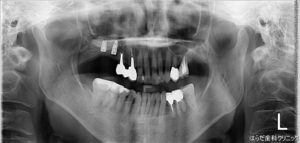

こちらもレントゲンをとって確認します。

こちらもしっかりと埋入されています。